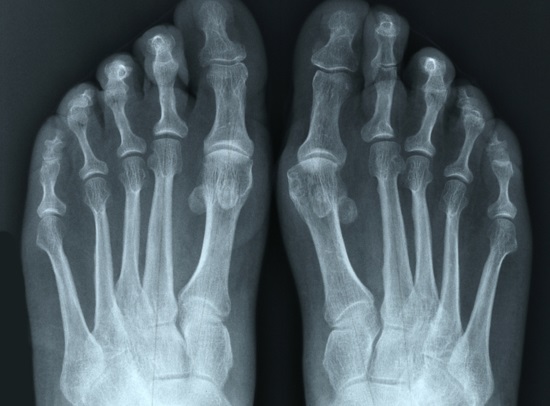

Поражение первого плюснефалангового сустава наблюдается при подагре. Артрит мелких суставов может возникать при ревматизме и аутоиммунных заболеваниях. Появление новых очагов воспаления или активизация уже существующих может быть вызвана следующими факторами:

Для оценки степени функциональных нарушений применяются специальные тесты. К аппаратным методам диагностики относятся компьютерная томография (КТ) и магнитно-резонансная томография (МРТ). Часто используется рентгенография сустава в различных проекциях. Обследование внутренних органов является обязательным этапом диагностики.

- деформация сустава, видимая на изображениях;